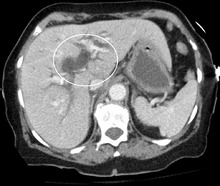

Biliary tract dilation due to obstruction as seen on CT scan (axial plane)

Most people presenting with jaundice will have various predictable patterns of liver panel abnormalities, though significant variation does exist. The typical liver panel will include blood levels of enzymes found primarily from the liver, such as the aminotransferases (ALT, AST), and alkaline phosphatase (ALP); bilirubin (which causes the jaundice); and protein levels, specifically, total protein and albumin. Other primary lab tests for liver function include gamma glutamyl transpeptidase (GGT) and prothrombin time (PT).[28] No single test can differentiate between various classifications of jaundice. A combination of liver function tests as well as other physical examination findings is essential to arrive at a diagnosis.[29]

Medical imaging such as ultrasound, CT scan, and HIDA scans are useful for detecting bile duct blockage.[32]